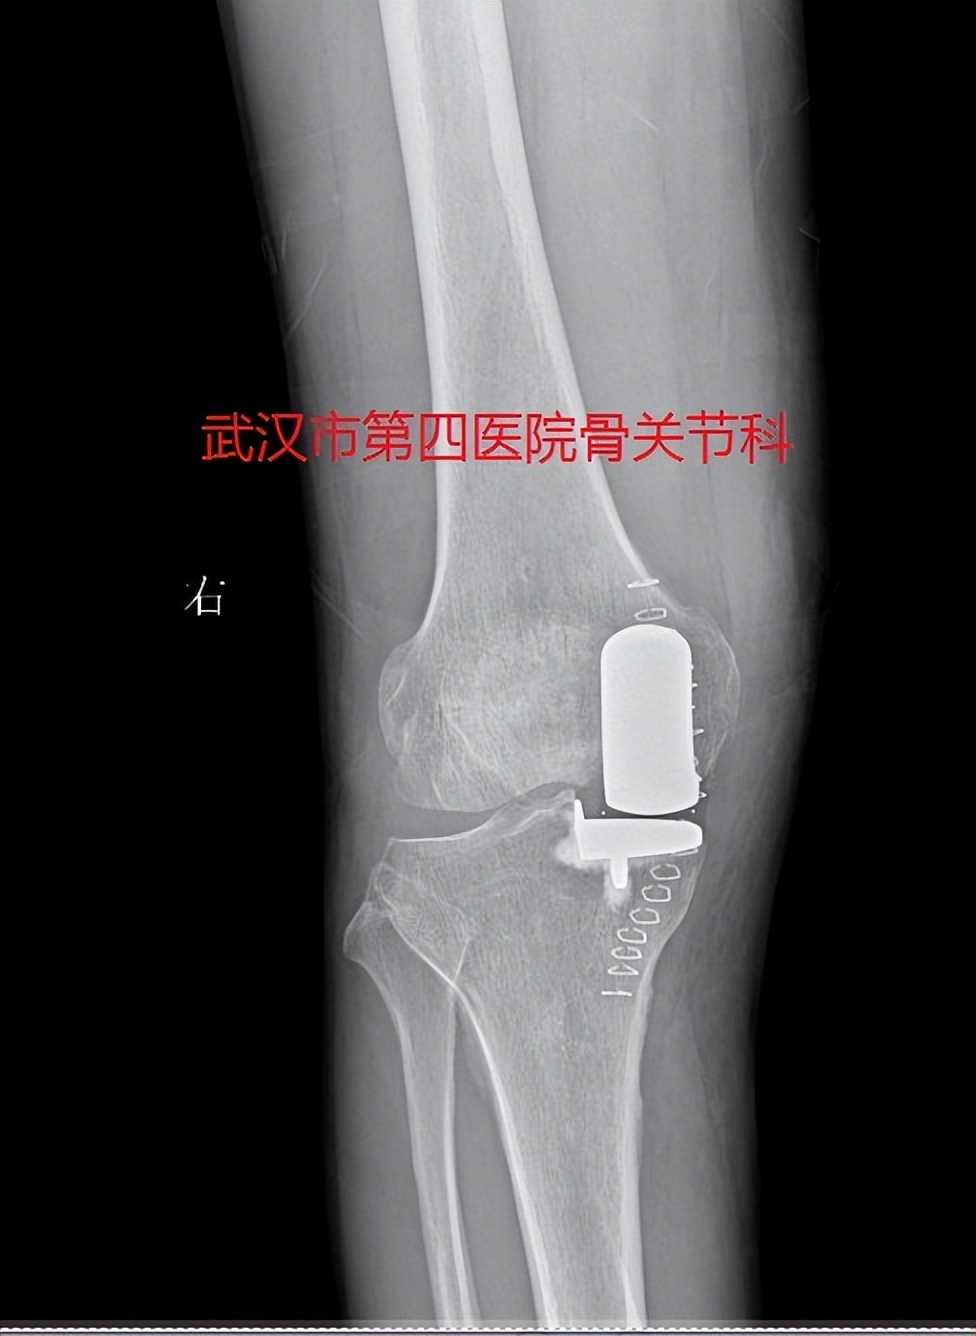

3.保膝手术-单髁置换术:如果膝关节骨关节炎是以单侧间室关节炎为主,可以考虑单髁置换术,分为内侧单髁置换和外侧单髁置换术

保膝治疗:膝关节内侧单髁置换

保膝治疗:膝关节外侧单髁置换